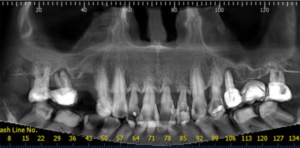

Figura 1 – Corte panorâmico de tomografia volumétrica do cone-bean. Observar o comprometimento de praticamente todos os elementos dentais superiores, devido à doença periodontal importante. Apenas os dentes 14, 13 e 23 poderiam ser mantidos.